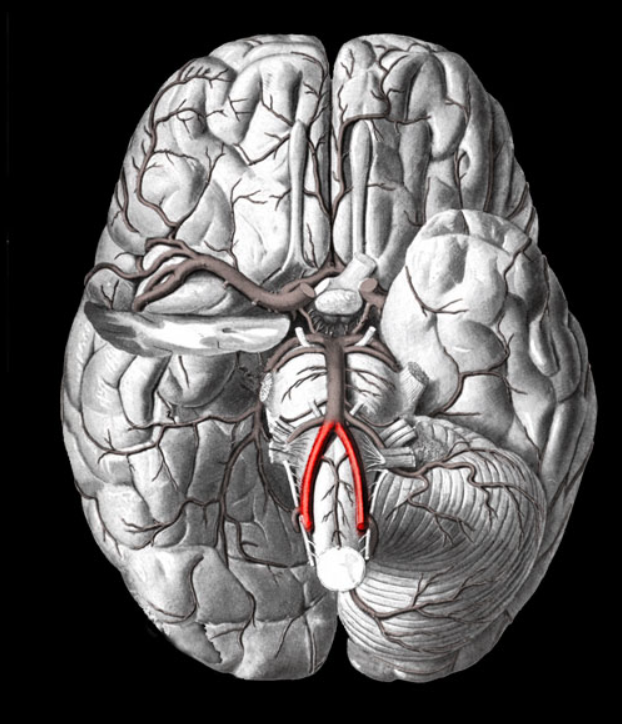

vertebral arteries

Basilar artery

internal carotid arteries

Arterial circle